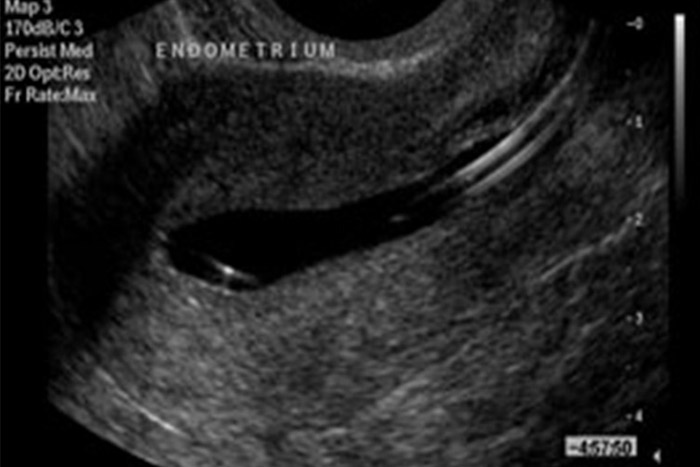

قبل از تزریق نرمال سالین محل کتتر تعیین می شود. با شروع تزریق امکان ورود حبابهای کوچک وجود دارد که با ادمه تزریق از بین می رود. پس از دیلاته شدن رحم بشکل متقارن وآندومتر با ضخامت یکنواخت دیده می شود. در هیستروسونوگرافی نرمال علائمی به نفع توده داخل یا خارج رحمی دیده نمی شود.پاساژ نرمال سالین بداخل حفره لگنی دلالت بر باز بودن حداقل یک لوله دارد.

پولیپ عبارت است از یک هیپر پلازی فوکال غدد و استرومای آندومتر که بشکل یک کانون اکوژن نسبت به بافت میومتر (نمای هایپر اکو) مشاهده می شود و غالبا نمای کیستیک ظریفی در داخل پولیپ وجود داردکه می تواند مطرح کننده وجود پایه خونرسانی در پولیپ باشد (1). مطالعات متعددی در رابطه با دقت تشخیصی پولیپ با روشهای سونوگرافی، هیستروسونوگرافی و هیستروسکوپی انجام گرفته است.

با استفاده از هیستروسونوگرافی تعداد و محل دقیق پولیپها مشخص می شود ،که راهنمای خوبی برای اجرای هیستروسکوپی است.